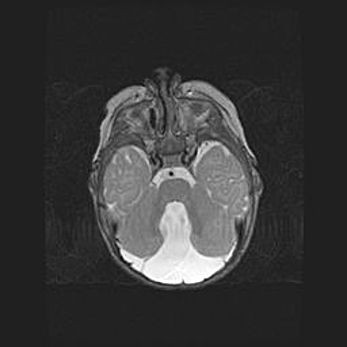

Церебральная ишемия II.

Возраст: 5 дней

Вес: 3400 г

Пол: женский

Окружность головы: 35 см

Срок гестации: 39 недель

Церебральная ишемия – это заболевание, характеризующееся недостаточностью (гипоксией) либо полным прекращением (аноксией) снабжения мозга кислородом по причине закупорки одного или нескольких сосудов. Это приводит к  что метаболическим расстройствам различной степени тяжести в тканях головного мозга, развитию коагуляционных некрозов и гибели нейронов.